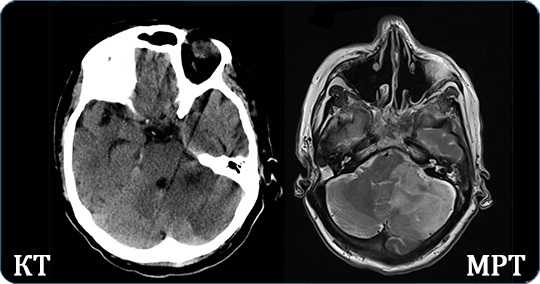

Для диагностики пороков сравнивают результаты КТ и МРТ